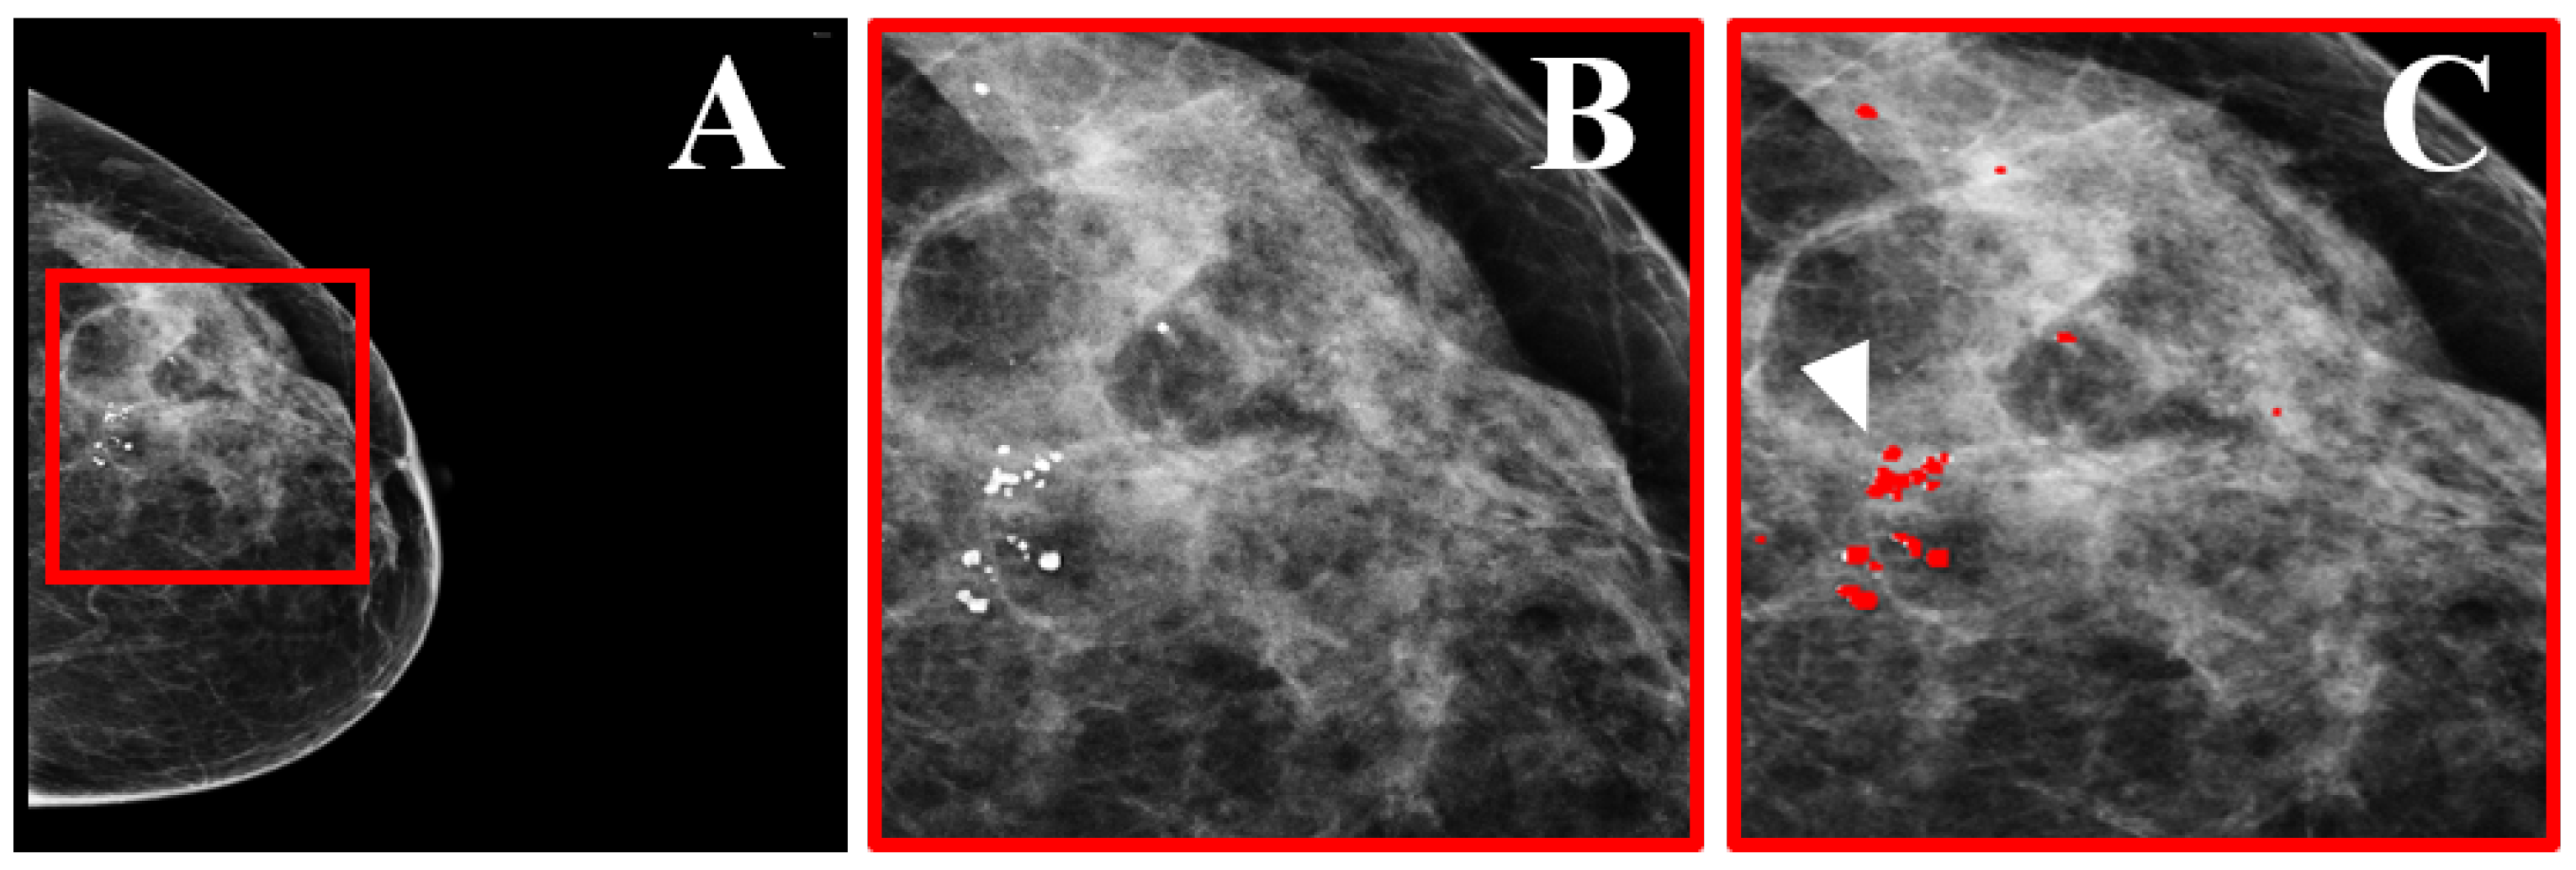

- Loizidou, K.; Skouroumouni, G.; Nikolaou, C.; Pitris, C. An automated breast micro-calcification detection and classification technique using temporal subtraction of mammograms. IEEE Access 2020, 8, 52785–52795. [Google Scholar] [CrossRef]

- Loizidou, K.; Skouroumouni, G.; Pitris, C.; Nikolaou, C. Digital subtraction of temporally sequential mammograms for improved detection and classification of microcalcifications. Eur. Radiol. Exp. 2021, 5, 1–12. [Google Scholar] [CrossRef]

- Loizidou, K.; Skouroumouni, G.; Nikolaou, C.; Pitris, C. Automatic Breast Mass Segmentation and Classification Using Subtraction of Temporally Sequential Digital Mammograms. IEEE J. Transl. Eng. Health Med. 2022, 10, 1–11. [Google Scholar] [CrossRef]